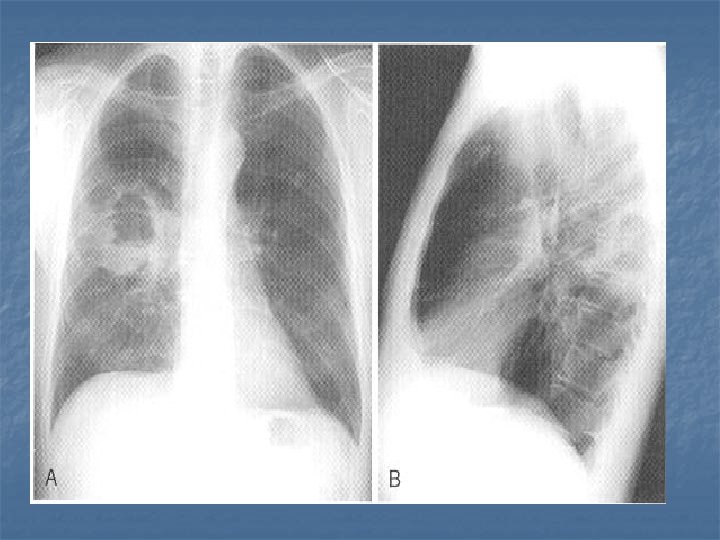

CXR Findings VIRAL n Peribronchial thickening n Diffuse interstitial infiltrates n Hyperinflation BACTERIAL n Subsegmental, segmental or lobar infiltrates n Air bronchograms n Round pneumonia in early S. pneumo n n M. pneumo diffuse infiltrates out of proportion to clinical findings (or bronchopneumonia infiltrates in lower lobes) Bilateral reticulonodular interstitial infitrates

n n n 50% bacterial pneumonia will have lobar infiltrate Can also see alveolar infiltrates Round pneumonia seen with S. pneumo